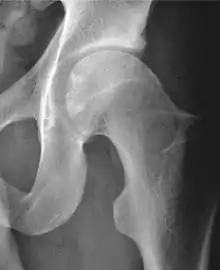

X-ray

Radiograph of a cam type impingement.